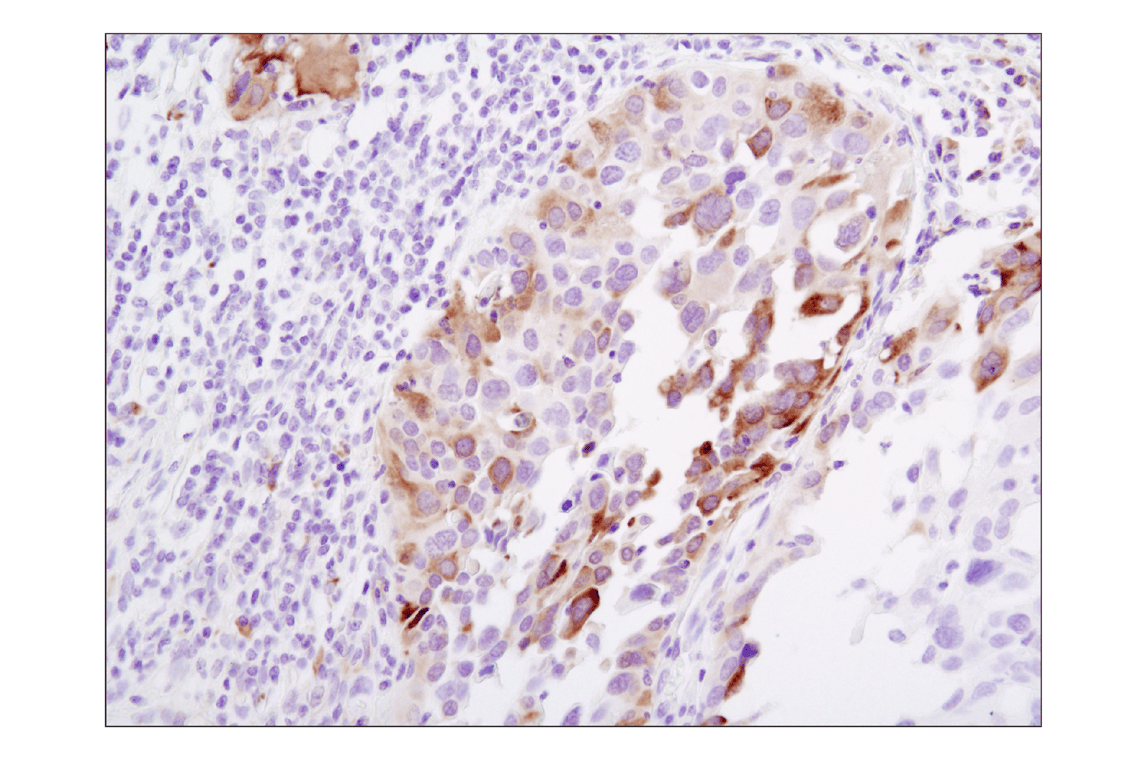

Immunohistochemical analysis of paraffin-embedded human lung carcinoma using Phospho-S6 Ribosomal Protein (Ser235/236) (D57.2.2E) XP® Rabbit mAb.

Immunohistochemistry Image 5: Phospho-S6 Ribosomal Protein (Ser235/236) (D57.2.2E) Rabbit Monoclonal Antibody